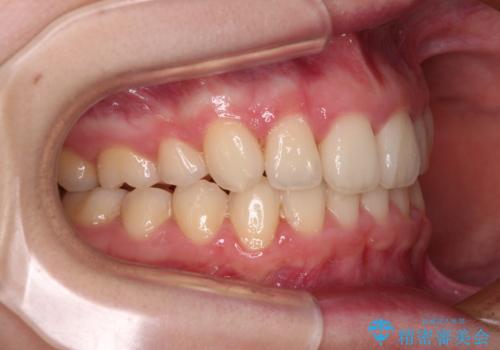

奥歯の咬み合わせがなかなか定まらず、スペースが閉じるまでに時間がかかりましたが、最終的には正中を合わせることもできました。

- 治療期間

- 2年5ヶ月